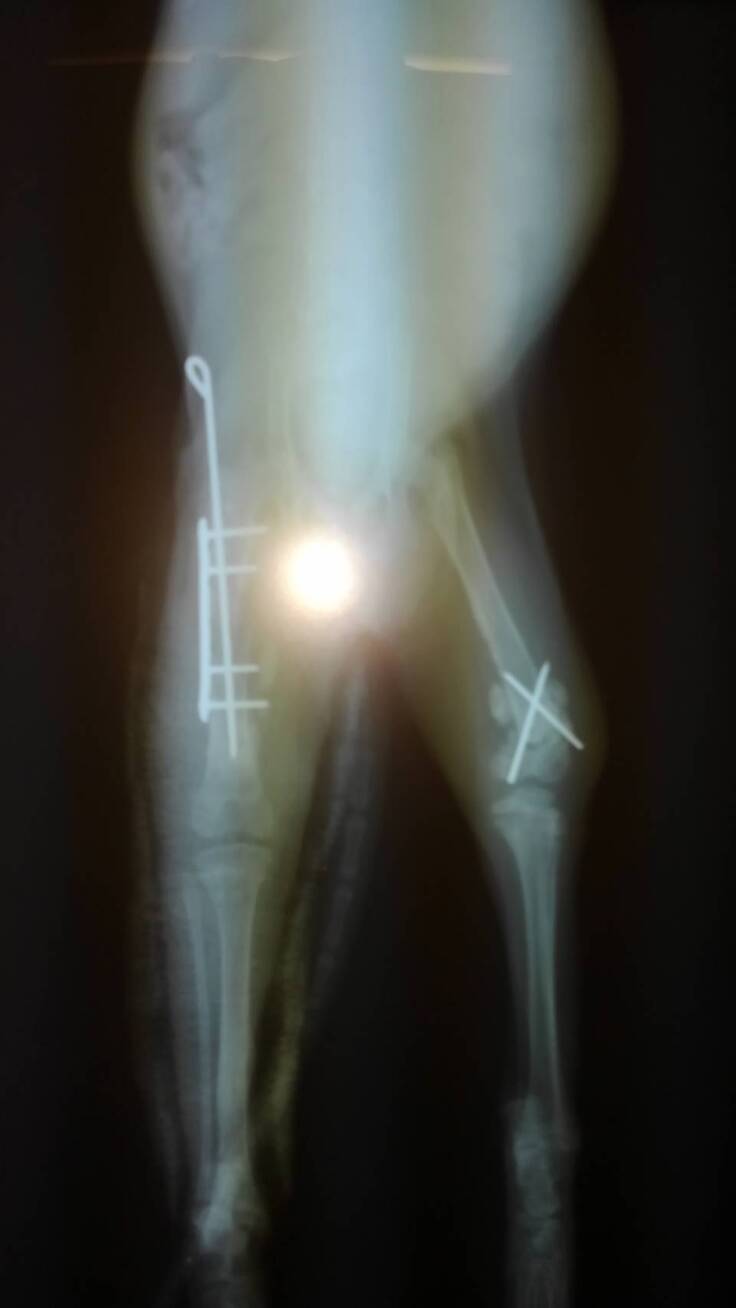

右後肢大腿骨骨幹はプレートで固定、左後肢大腿骨遠位端はクロスピンで固定。

⑥再手術10/15(土曜日)B動物病院

もうすぐ退院と思いきや何と!まさか?右大腿骨のプレートが外れてしまい再手術。

今回はプレート+サポートピンで念入りに固定してくれ無事に成功。生後2ヵ月ほどの小さな子猫なので骨が細く大変難しい手術だと思います。先生に感謝!!。

(レントゲン写真はB動物病院から許可を得て掲載しています。)